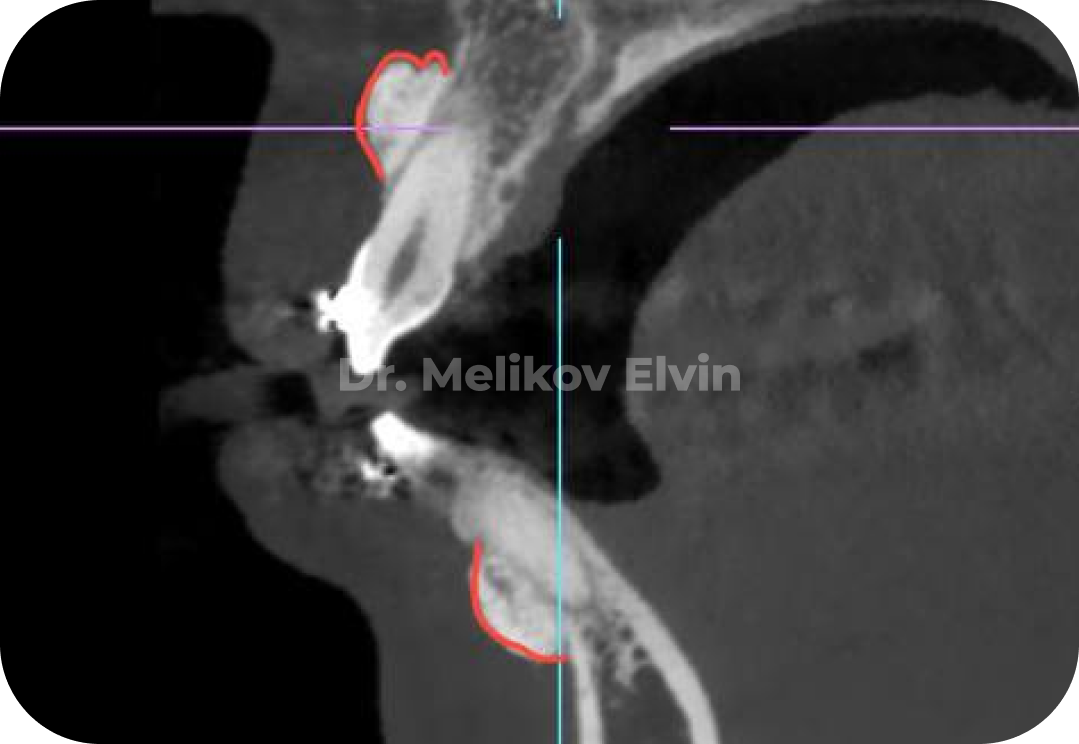

На снимках можно увидеть воссозданный объём наружной кортикальной пластинки в проекции корней зубов.

После костной пластики на двух челюстях